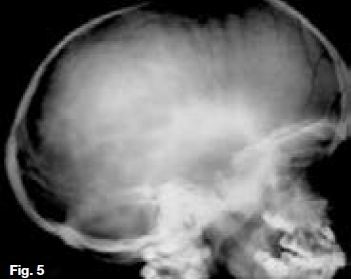

Hypovitaminosis D leads to nondeposition of calcium salt in bone matrix. Figure 5 is a lateral skull radiograph showing generalized radiolucency while figures 6 & 7 are intra-oral and bitewing radiographs of the same patient showing large pulp cavities (green arrow) and attenuation of the lamina dura and dental crypts (yellow arrow). There is also lack of mineralization of the alveolar crest bone (blue arrow). These radiological features are suggestive of Vitamin D-resistant rickets which is an isolated renal tubular defect inhibiting reabsorption of inorganic phosphates, resulting in hypophosphaturia which is inherited as an X-linked dominant trait. The full manifestation of vitamin D-resistant rickets is rickets or osteomalacia non-respondent to vitamin D therapy, as vitamin D metabolism is normal. However, there is diminished intestinal calcium and phosphate absorption. Patients with the milder form may be slightly shorter than normal siblings, with no other manifestation. Females with vitamin D resistant rickets tend to show fewer signs and symptoms than do their brothers.